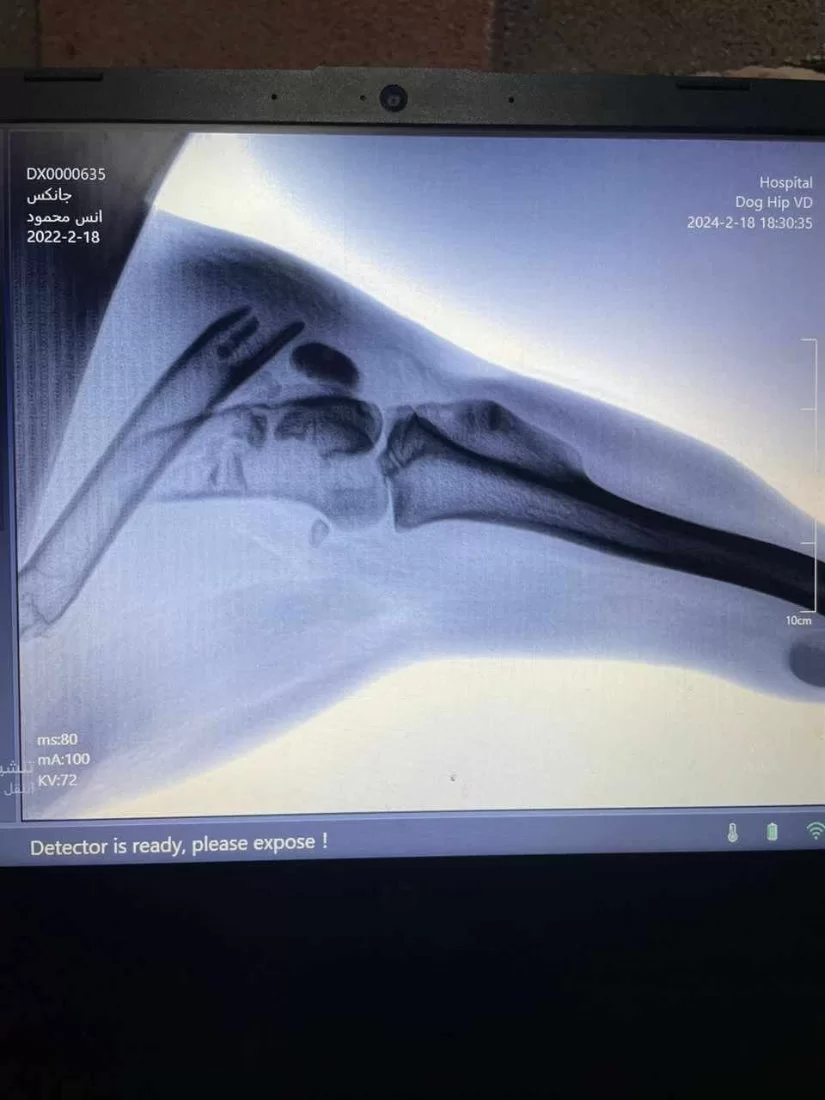

عملية تثبيت كسر مركب في كلب مالينو ( الراعي البلجيكي)

تم اليوم الموافق 21 فبراير 2024 إجراء عملية جراحية لكلب يعاني من كسر مركب في منطقة الركبة حيث قام اساتذة القسم بالتعاون مع طلبة السنه الخامسة من تثبيت الكسر بواسطه أسياخ بلاتينية وايضا تم استخراج اجسام غريبة كانت قد اخترقت الجلد اثناء تعرض الحيوان للحادث. وتاتي هذه الانشطه ضمن دور كلي